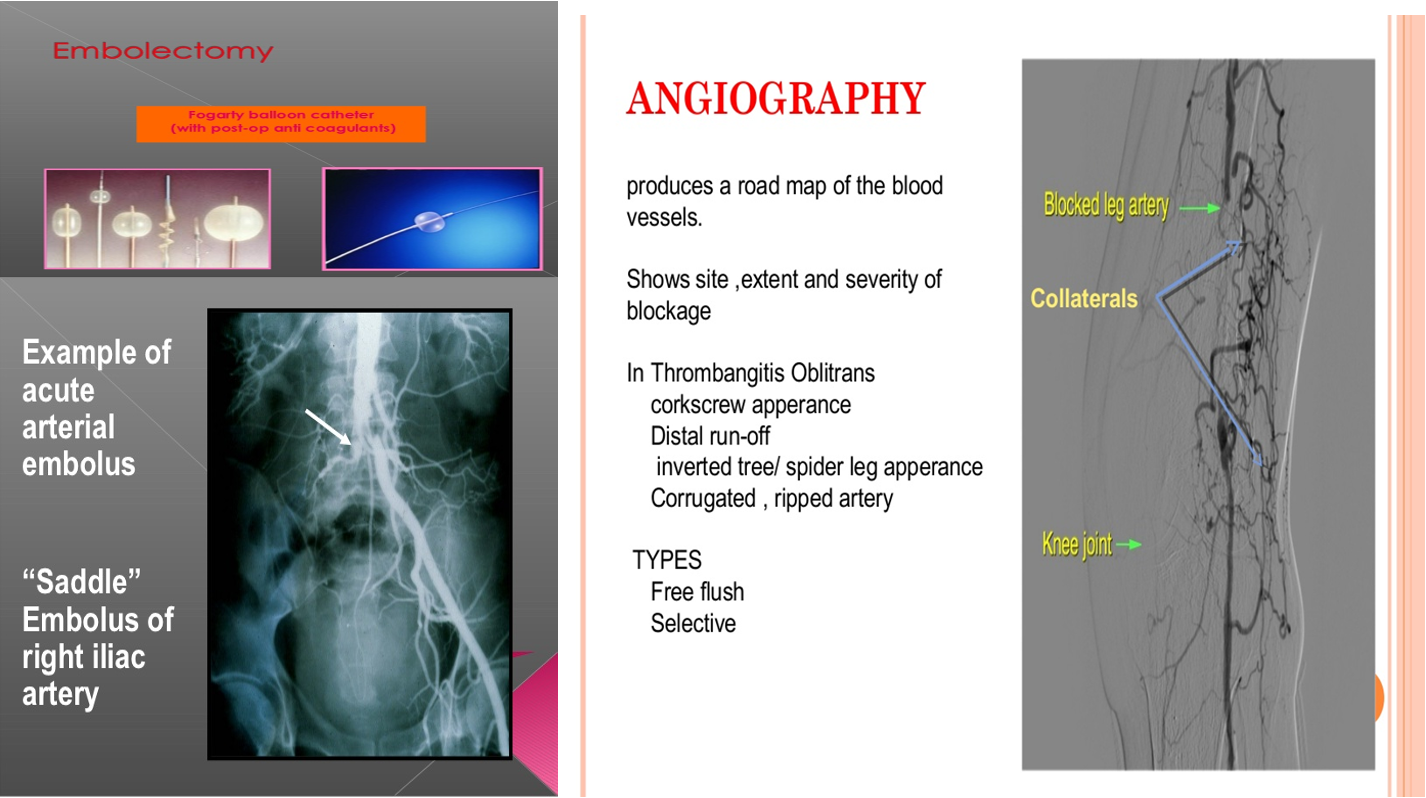

2nd Modality: Angiography Findings: complete blockage of right common illiac, saddle embolus Diagnosis: chronic ischemia

3rd Modality: Angiography Findings: collaterals and distal runoff Diagnosis: chronic ischemia